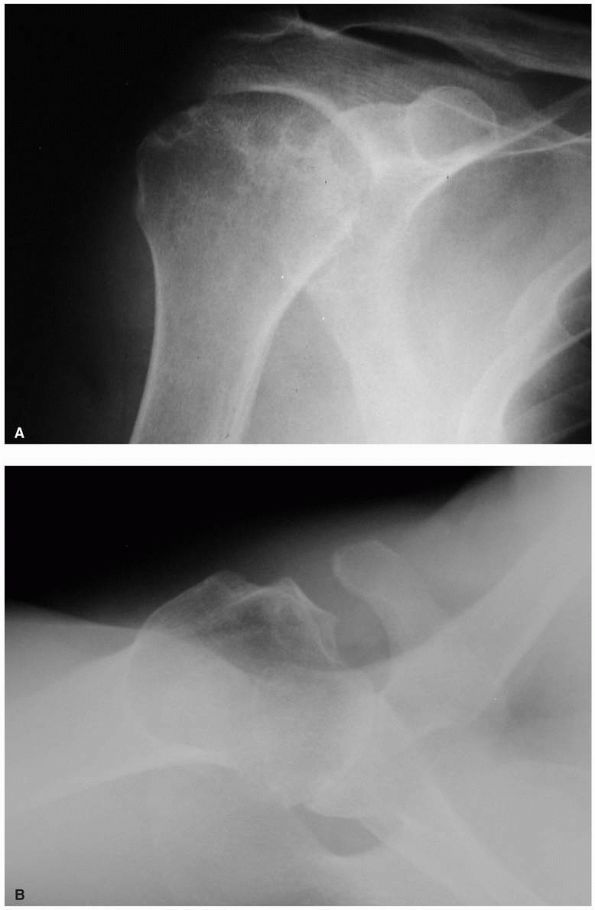

share similar roentgenographic features. Plain radiographs in the AP

and axillary planes are usually sufficient to evaluate the extent of

disease. The absence of articular cartilage manifests as a loss of the

joint space along with sclerosis of the subchondral bone and

subarticular cysts in both the humerus and glenoid. Flattening of the

humeral head and large peripheral osteophyte formation, particularly

along the anterior and inferior margins, results in an apparent

increase in the head diameter. Although rotator cuff tears are uncommon

in primary osteoarthritis, as previously mentioned, maintenance of the

subacromial space provides a simple initial indicator of rotator cuff

integrity (Figure 12-7).

FIGURE 12-7. Glenohumeral osteoarthritis. (A) Anteroposterior radiograph demonstrating joint space narrowing (large black arrow), osteophyte formation (large white arrows), and subchondral cysts (small black arrows). (B) Axillary view showing typical posterior glenoid wear (large black arrows)

and posterior subluxation of the humeral head. The small black arrows indicate normal points of contact between the head and the glenoid. |